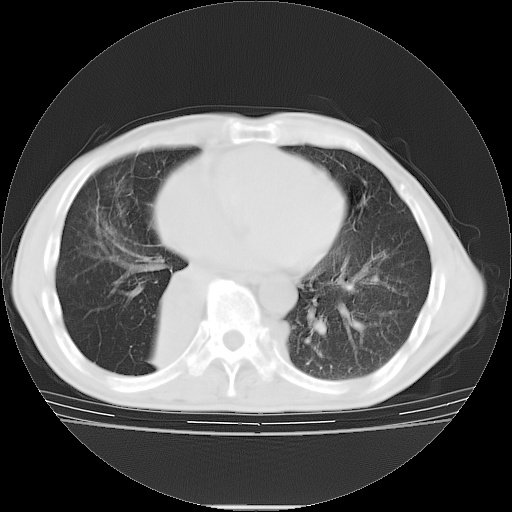

男性患者,63岁。右侧胸背部疼痛2月,加重一周。

考虑:右肺中央型肺癌并右肺下叶不张;两肺尖继发性肺结核。

还有纵隔多处肿大淋巴结及肋骨的改变、两肺多发结节灶。

右肺下叶支气管狭窄闭塞,右下肺不张,气管前间隙淋巴结肿大,两上肺散在分部粟粒灶,沿肺血管支气管束分部,血管支气管束走形较为光滑。考虑右肺中心型肺癌合并肺不张,纵隔淋巴结转移,两上肺癌性淋巴管炎

右肺下叶中心性肺癌并纵隔淋巴结转移,左侧肋骨转移。双肺上叶继发性结核表现。

1)右肺下叶中心性肺癌并纵隔淋巴结转移,两肺转移,左侧肋骨转移。2)双肺上叶继发性结核。

右肺下叶中心性肺癌并纵隔淋巴结及两肺、左侧肋骨转移。双肺上叶继发性结核表现。